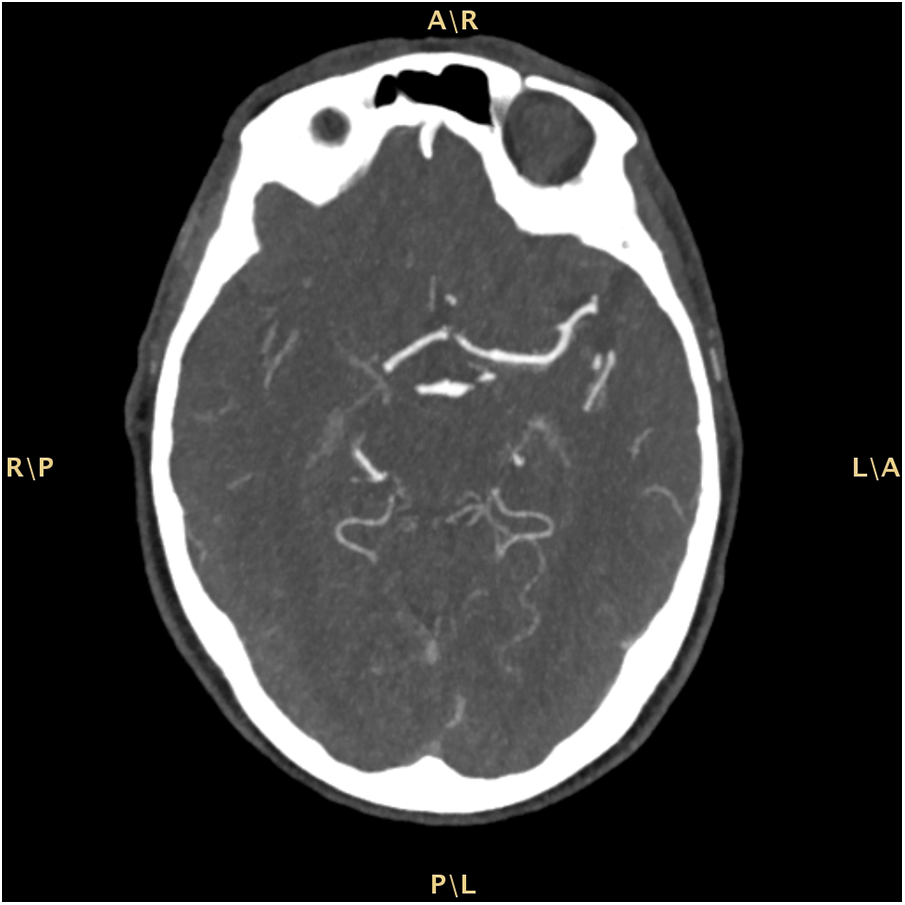

The patient was admitted to our Emergency Department (ED) due to a sudden onset of left hemisyndrome and deviation of gaze to the right, as witnessed by family members. Past medical history included a previous tuberculosis with right-sided cavitation and transthyretin cardiac amyloidosis diagnosed in May 2022 — i.e., suggestive echocardiographic findings with left ventricular hypertrophy without cardiac kinetic abnormalities; absence of monoclonal serum component in blood chemistry and urinary tests; supported by a bone scintigraphy with cardiac hyperuptake (Perugini score 3). Moreover, the patient was undergoing antihypertensive and anxiolytic therapies. White blood cell count and hemoglobin were within the normal ranges. Renal and liver function tests were normal. Pre-stroke mRS score was 1. A computed tomography (CT) scan of the brain showed a malacic area limited to the left mesial frontal region, traceable to an ischemic event in the region of the distal branches of the ipsilateral anterior cerebral artery (Alberta stroke program early CT score, ASPECTS 9). A CT angiography of the cerebral-afferent vessels combined with a perfusion study showed no recognizable opacification in the M1 section of the right middle cerebral artery, due to thrombotic occlusion. The perfusion study revealed abnormal Tmax and cerebral blood flow (CBF) values in the volume of parenchyma studied with a mismatch of approximately 21.3, due to the presence of a large area of ischemic penumbra in the region of the right middle cerebral artery (Figure 1). The neurological exam performed in the ED showed a lack of leveling of the left upper limb and sagging of the left lower limb, and fluent speech albeit with dysarthria (National Institutes of Health Stroke Scale, NIHSS 12). Since there were no contraindications, systemic thrombolysis was performed for a weight of 73 kg, total dose 65.7 mg (10% bolus, 1 hour of continuous infusion). The patient was later transferred to the angiography suite to undergo mechanical thrombectomy, with manual thromboaspiration of the organized red thrombus. The final control angiography showed complete recanalization of the right middle cerebral artery (modified thrombolysis in cerebral infarction, mTICI 3). Finally, the patient was admitted to the Stroke Unit. During hospitalization the patient remained haemodynamically stable, with good respiratory exchange and afebrile. The electrocardiogram (ECG) showed a first-degree atrioventricular block, right bundle branch block and left anterior fascicular block. The patient was under continuous electrocardiography monitoring throughout her stay (4 days) in the Stroke Unit after the acute event, and no atrial fibrillation was detected. Vital parameters remained normal and stable during hospitalization. The control brain CT scan performed on the first day of hospitalization confirmed an ischemic lesion in the right internal capsule. A neurosonological study of the intracranial and cerebral-afferent vessels to ascertain its etiology, confirmed the patency of the right middle cerebral artery whereas there was a significant stenosis before the procedure. Furthermore, a resting echocardiography also revealed only moderate left atrial dilatation and mild mitral regurgitation. Finally, a 24-h Holter monitor detected no occult arrhythmias. A full cardiological evaluation recommended continuation of the ongoing follow-up for cardiac amyloidosis. Acetylsalicylic acid was initiated as secondary prevention therapy and atorvastatin was also introduced at low dosage due to the vascular pleiotropic effect. A Doppler ultrasound of the supra-aortic trunks revealed an extracranial finding of mild stenosis of the carotid bifurcation and at the origin of the right external carotid artery and the Doppler ultrasound of the intracranial vessels instead was within normal limits. The patient underwent cycles of kinesiotherapy with good response. The discharge neurological exam showed a clear improvement: a slight weakness of the left lower extremity and a slight impairment of the left seventh cranial nerve persisted. The patient walked unassisted with the aid of a walker and was fed orally with a soft diet and free fluids.

Figure 1

Computed tomography (CT) scan of the brain.